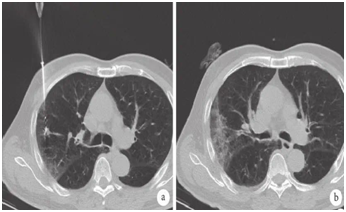

患者微波消融術中和術后即刻 CT 檢查表現(xiàn)

近期,馬鞍山市人民醫(yī)院胸心外科在麻醉科、CT室的協(xié)助下,連續(xù)成功為3例肺部小結節(jié)患者作了微創(chuàng)微波消融術。3例病變均在1cm左右(兩例實性結節(jié),1例磨玻璃結節(jié))。術前對小結節(jié)作充分的討論分析,術中精確定位、穿刺活檢,并進行精準消融治療,術后未發(fā)生任何并發(fā)癥,次日出院。